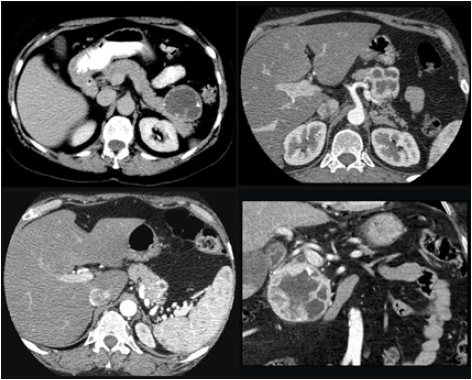

Özel bir hormon salgılamadıkları için ameliyat öncesi tanıları her zaman olanaklı değildir. Ayrıca bu ayrımın yapılması her zaman gerekli de değildir. Pankreasta eğer kistik olmayan solid bir kitle saptanırsa yaklaşım ameliyata engel özel bir durum olmadığı sürece cerrahidir. Pankreasın diğer organlarda görülebilen iyi huylu ve çıkartılması gerekmeyen bir kitlesi yoktur.

Bu nedenle fonksiyon göstermeyen tüm endokrin tümörlerde boyutlarına bakılmaksızın cerrahi olarak çıkartılırlar. En önemli avantajları 3 cm’den küçük olduklarında pankreas kanserinde olduğu gibi büyük cerrahi gerektirmeden çıkartılabilmeleridir. Ancak bölgesel lenf bezlerinde tutulum olduğu düşünülürse pankreas kanseri gibi davranılmalıdır.

Endokrin tümörler pankreas kanserine göre daha iyi seyirlidirler. Ancak onlarda uzak organlara yayılabilirler ve zaman zaman pankreas kanseri gibi seyredebilirler.

Karaciğer metastazı(yayılımı) olan PET’lerde eğer metastazlar teknik olarak çıkartılabiliyorsa pankreas tümörüyle birlikte çıkartılmaları en doğru yaklaşımdır. Ancak cerrahi olarak çıkartılamayan tümörlerde alternatif yöntemler uygulanır